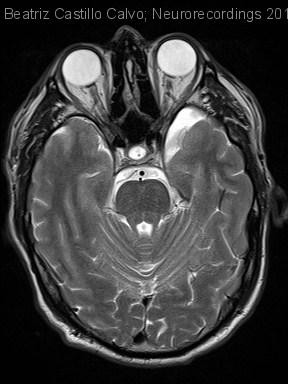

Diagnóstico final: POSIBLES SCHWANNOMAS V2 BILATERALES

Varón de 49 años, sin antecedentes personales ni familiares de interés, no hábitos tóxicos y no toma de fármacos de forma habitual. Presenta episodios repetidos y autolimitados de neuralgia y parestesias en región V2 izquierda desde...